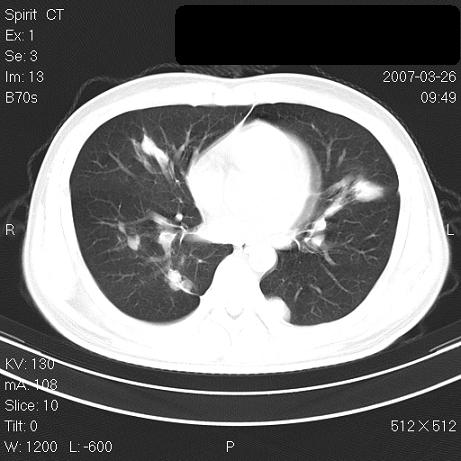

标题: CT7171B:补充治疗后2周复查 [打印本页]

标题: CT7171B:补充治疗后2周复查

治疗后2周复查,请讨论

结合以前的ct片,还是考虑肺挫伤,吸收多了。

支持:创伤性湿肺。现肺挫裂伤(出血 积气)大部分吸收。建议继续治疗!

结合以前的ct片,支持创伤性湿肺。现大部分吸收。

支持:创伤性湿肺、肺挫裂伤。现肺挫裂伤(出血、渗出、液气腔)大部分吸收。建议继续治疗!

支持:创伤性湿肺、肺挫裂伤。现肺挫裂伤(出血、渗出、液气腔)大部分吸收.

经治疗后病灶明显吸收,考虑创伤性湿肺、肺挫裂伤